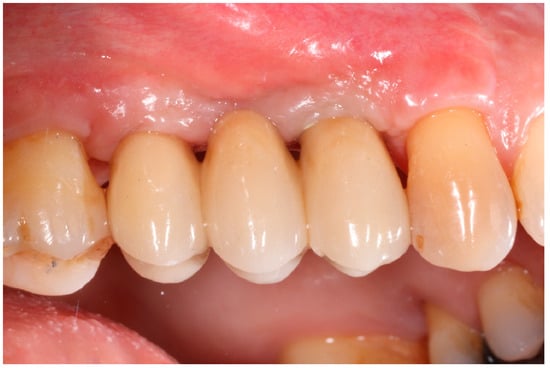

Healing abutments were screwed to the implants and the flaps were sutured. Additional peri-implant plastic surgery procedures (connective tissue grafts or free gingival grafts) were performed when needed in order to have at least 2 mm of attached keratinized mucosa. The prosthetic phases began upon healing of the soft tissues, and definitive screw-retained prostheses were finally delivered (Figure 11, Figure 12 and Figure 13).

Figure 11. Delivery of definitive prosthesis.

Medicina 61 01814 g011